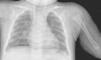

Posteriormente, se comprueba una hipofosfatemia, valores altos de fosfatasa alcalina y de hormona paratiroidea, y bajos de vitamina D compatibles con raquitismo carencial (tabla 1). El ionograma en orina fue normal. La radiografía de tórax y extremidades evidencia signos de raquitismo (fig. 1). Se inicia tratamiento sustitutivo con calcio (a dosis de 70mg/kg/día), calcitriol (a dosis de 100ng/kg/día) y vitamina D (3.000UI/día), y durante las convulsiones se administra gluconato cálcico al 10% (0,5ml/kg en 30min). Presenta progresivamente una mejoría clínico-analítica. El paciente recibió el alta hospitalaria al décimo sexto día de ingreso manteniendo niveles de calcio correctos en controles posteriores.

Caso Clínico 2. Lactante de 7 meses, de origen marroquí y sexo masculino que en las últimas horas realiza 3 episodios de hipertonía generalizada con desviación de la mirada. En los días previos presenta cuadro de dificultad respiratoria orientado como laringitis con irritabilidad marcada. Hijo de padres consanguíneos de origen marroquí, alimentado con lactancia materna habiendo iniciado alimentación complementaria. Desde el nacimiento recibe poca exposición solar. Al ingreso presenta un peso de 8,5kg (p50) y talla de 68cm (p50). En la exploración física presenta irritabilidad y estridor inspiratorio siendo el resto de la exploración normal. La analítica de sangre revela un calcio total e iónico de 5,6mg/dl y 0,61mmol/l respectivamente, con niveles aumentados de fosfato, fosfatasa alcalina y parathormona (tabla 1). El ECG muestra presenta ritmo sinusal con ondas T picudas y intervalo QT corregido discretamente alargado. Se realiza una serie esquelética que detecta alteraciones metafisarias compatibles con raquitismo (fig. 2). Con la orientación diagnóstica de raquitismo carencial se inicia tratamiento sustitutivo (calcio 80mg/kg/día, calcitriol 90ng/kg/día, vitamina D 3.000UI/día y gluconato cálcico 10% de rescate 0,5ml/kg en 30min). El estudio del metabolismo del calcio en la madre es normal. Durante el ingreso presenta buena tolerancia al inicio de la alimentación complementaria con cereales y una corrección favorable de la hipocalcemia. A los 9 días de ingreso recibe alta hospitalaria, realizándose seguimiento en consultas externas.